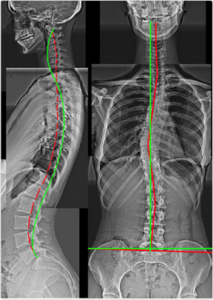

Case 1 — 37yo Male: Posture & Hip Tightness

Figure 1. Right Thoracic Lean, Right Head Translation, Increased Pelvic Tilt, Lumbar Hyperlordosis, Thoracic Hyperkyphosis, Anterior Head Translation, Cervical Hypolordosis. Multiple intersecting deformities — none detectable without X-ray